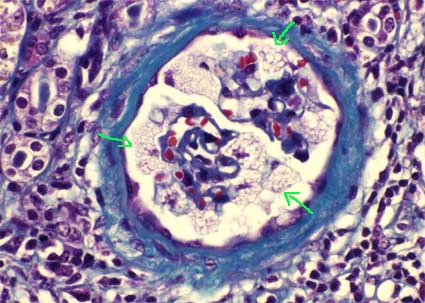

Histopathology

The glomeruli are the main site of injury. There is mesangial expansion and thickening of capillary walls. There are foamy cells in mesangium and capillaries and small holes are seen in the capillary walls, giving an aspect of membranous GN (Figures 10 and 11). You can also see images in double contour and "spikes". There may be segmental sclerosis. In the interstitium we can also find foam cells.

Figure 10. Foam cells, areas with empty appearance and intracapillary hyaline accumulations, which give an unusual appearance to the glomerulus, alterations very suggestive of LCAT deficiency. (H&E, X400).

Figure 11. Irregular capillary walls, with holes. Sometimes we can see spikes that suggest membranous GN; double contours can also be seen, with appearance of membranoproliferative GN. (Methenamine-silver, X400)